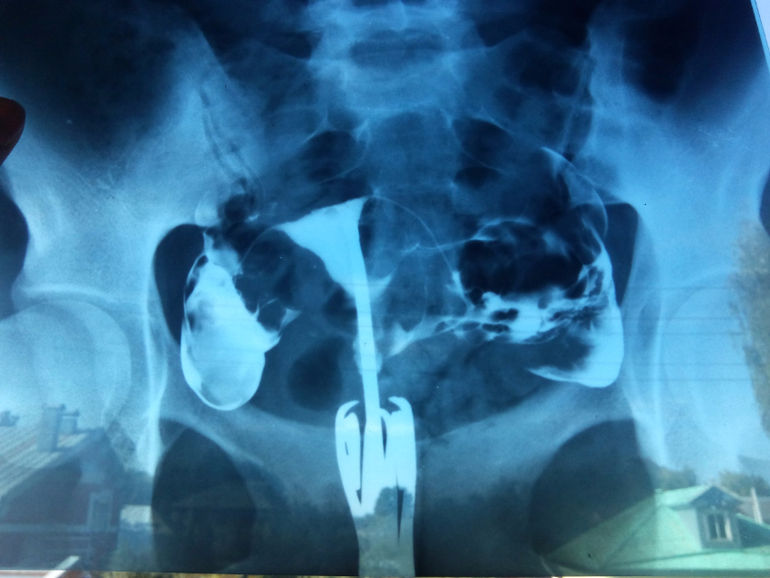

результат ГСГ

ГСГ, ЭХО, МСГ, Фертилоскопияподскажите пожалуйста!!! планируется стимуляция овуляции. можно ли стимулироваться ? трубы ведь проходимы...

я посмотрела ваши снимки с ГСГ,...такие хорошие получились,ровненькие ))и видно все прекрасно))

Да, ровные-то ровные, но врача смутило, что они вверх смотрят, а не вниз, и матка сильно кзади отклонена (но при этом он ее инструментами смог поднять - думаю, были бы спайки, я бы от боли орала без анастезии-то...). В общем, достали они меня все, морально настраиваюсь, хотя гинеколог говорит, что лучшее для меня лекарство - шампанское перед овуляцией

Трубы проходимы, и это отлично) стимулироваться можно, если нет кист. Сходите на узи на 4-5 дц перед стимуляцией, и если кист нет, можно смело стимулироваться) желаю вам удачи)))